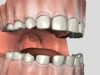

Missing Permanent Teeth